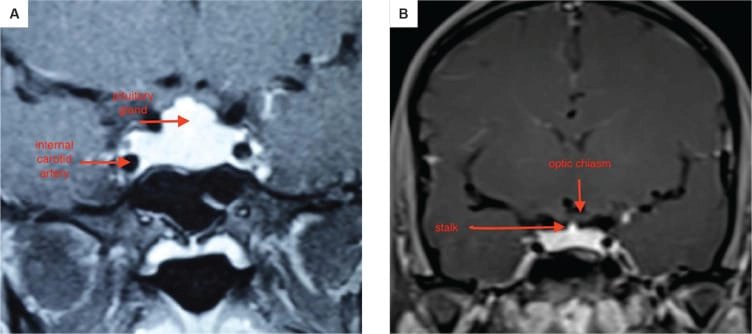

১. অবস্থান ও গঠন: পিটুইটারি গ্রন্থি একটি হাড়ের গঠন, যাকে সেলা টার্সিকা বলা হয়, তার ভিতরে বসে থাকে। এটি মাথার খুলির নিচের দিকে, স্ফেনয়েড নামক হাড়ে একটি গহ্বর, যা নাকের পেছনে অবস্থান করে। এটি অপটিক কায়াজম (optic chiasm) এর নিচে অবস্থিত, যেখানে দুটি চোখের স্নায়ু পরস্পর ক্রস করে। এটি ইন্টারনাল ক্যারোটিড আর্টারি নামক দুটি প্রধান রক্তনালীর মাঝখানে থাকে।

পিটুইটারি গ্রন্থি দু’টি প্রধান ভাগে বিভক্ত: অ্যান্টেরিয়র (সামনের) ও পোস্টেরিয়র (পিছনের) লোব। মানুষের ক্ষেত্রে ইন্টারমিডিয়েট লোব থাকলেও তা স্বতন্ত্র অংশ হিসেবে গঠিত নয়। অ্যান্টেরিয়র লোব অপেক্ষাকৃত বড় এবং পুরো গ্রন্থির প্রায় ৮০% ওজন ধারণ করে।